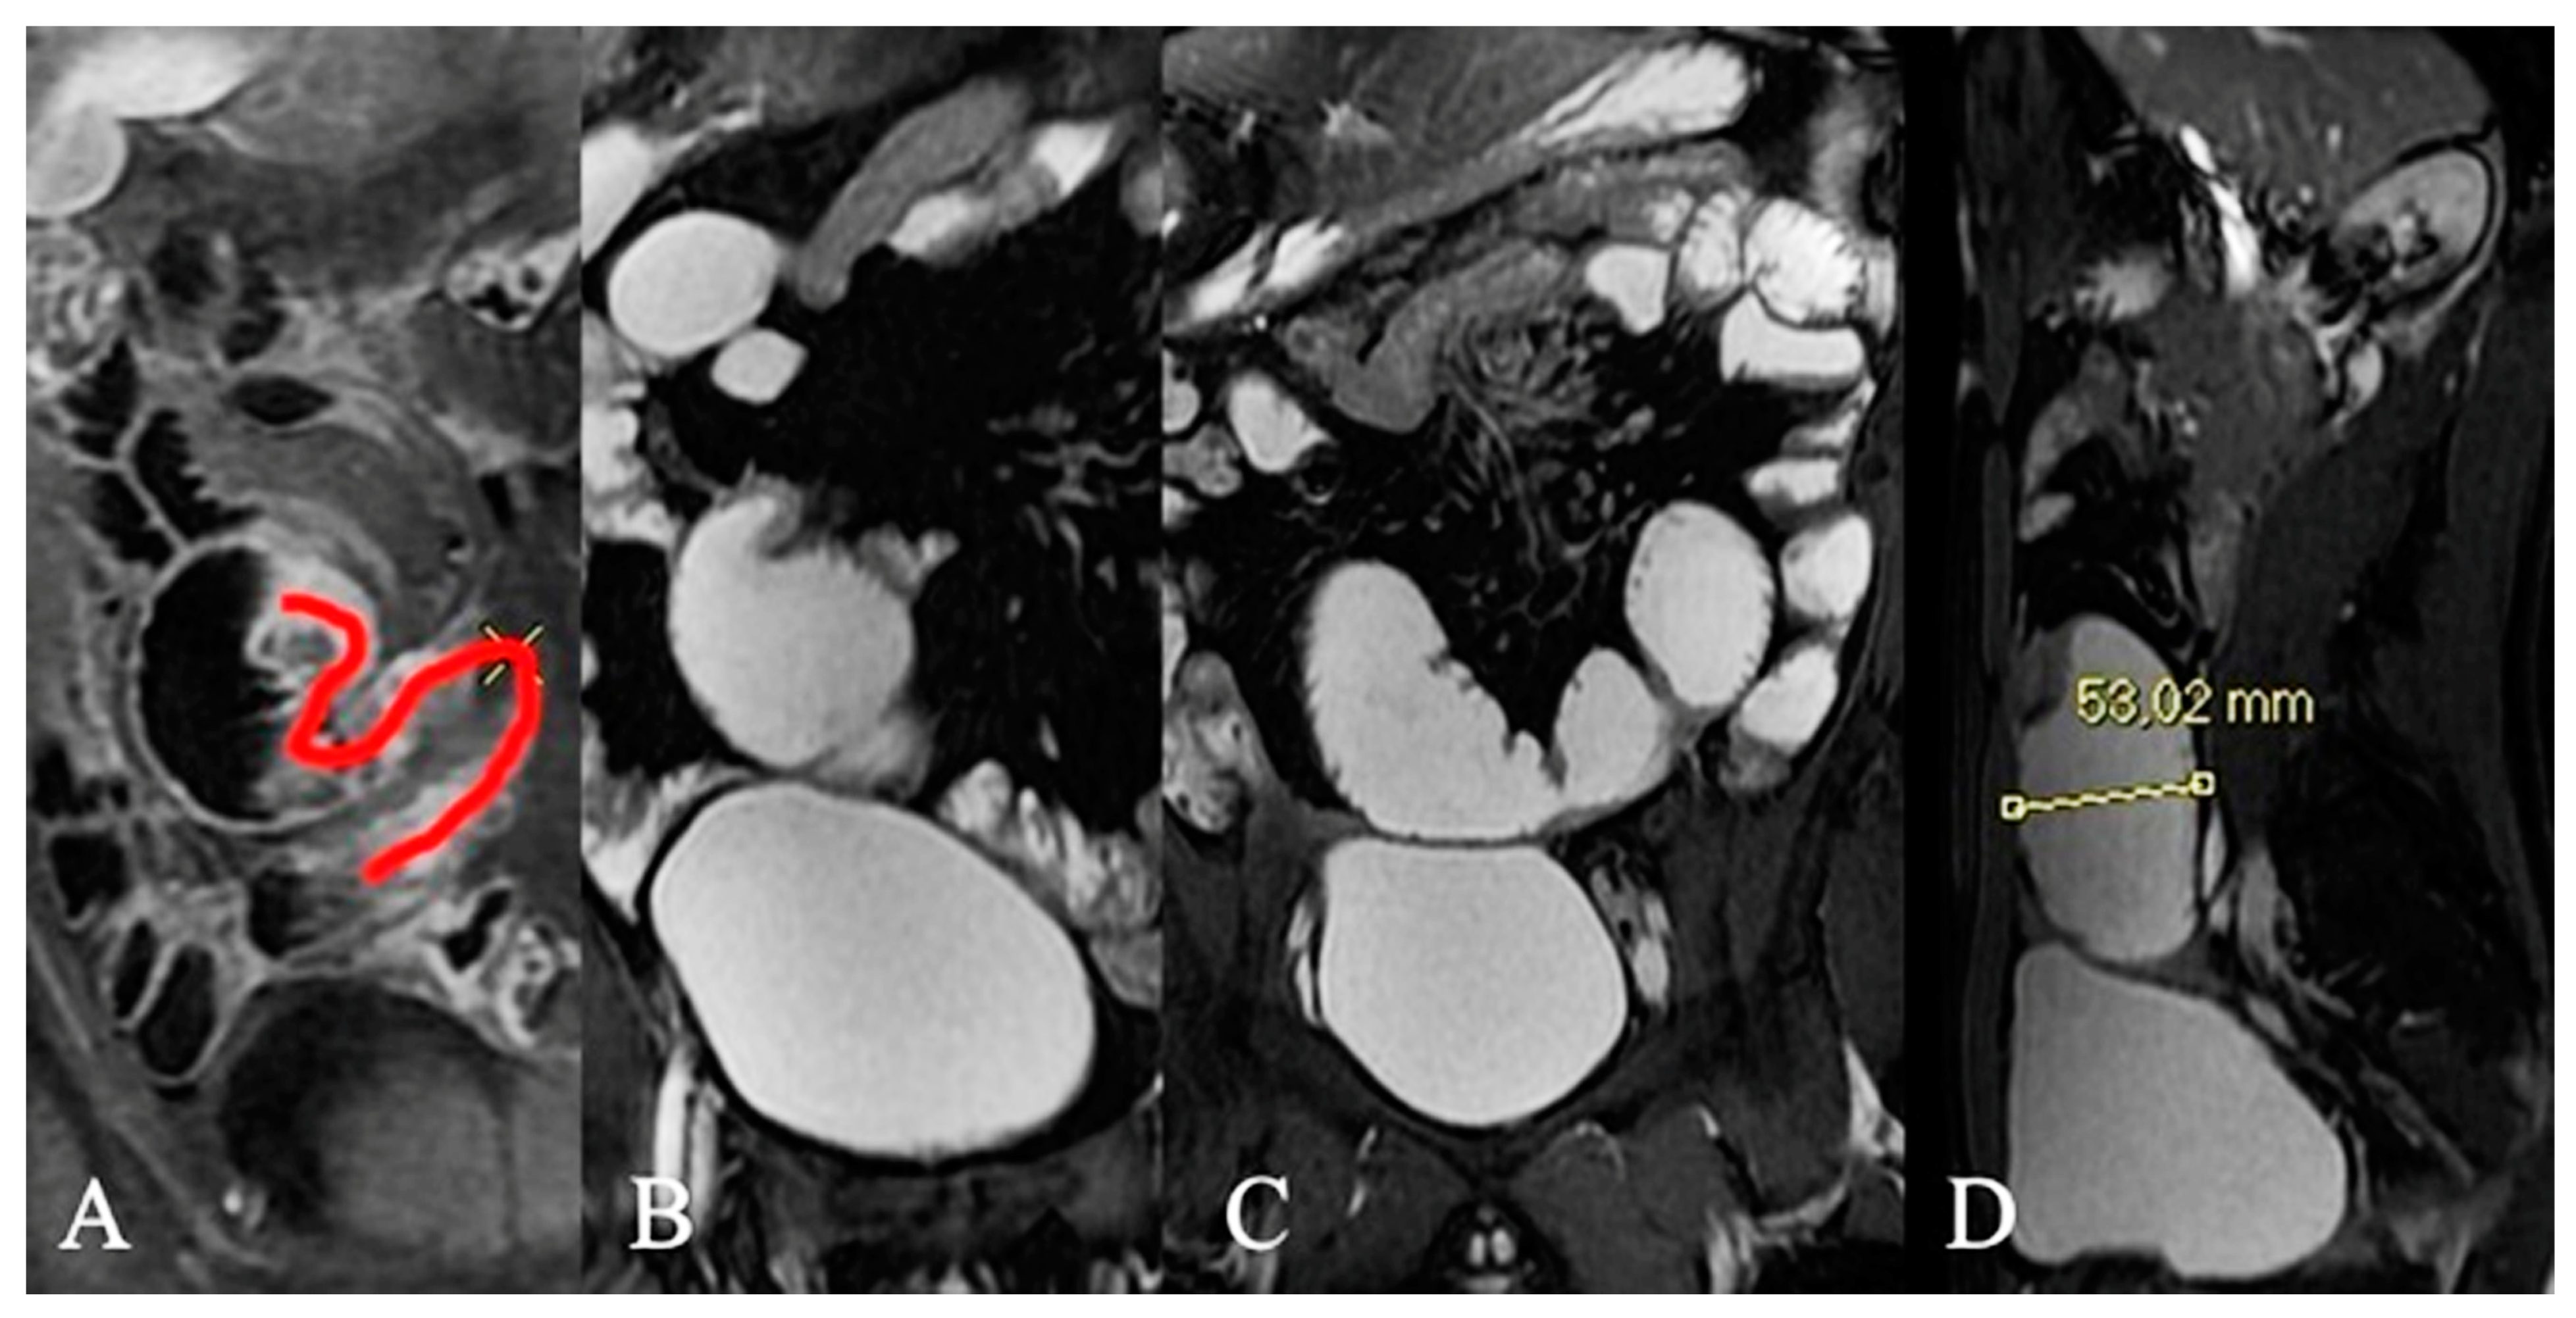

- Pierro, A.; Rotondi, F.; De Ninno, M.; Sallustio, G. Pseudodiverticular exophytic growth of a GIST of the jejunum with focus on imaging. Dig. Liver Dis. 2018, 50, 722. [Google Scholar] [CrossRef]